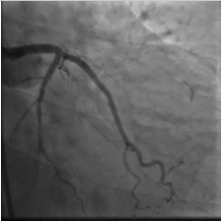

造影结果

2015年10月23日:左主干远段30%狭窄;左前降支近段支架自开口完全闭塞;左回旋支中段长病变,狭窄40%~50%,高位钝缘支粗大,未见狭窄(图1)。右冠粗大、优势型,近段管壁不规则,左室后支、后降支未见狭窄(图2、3)。

图1